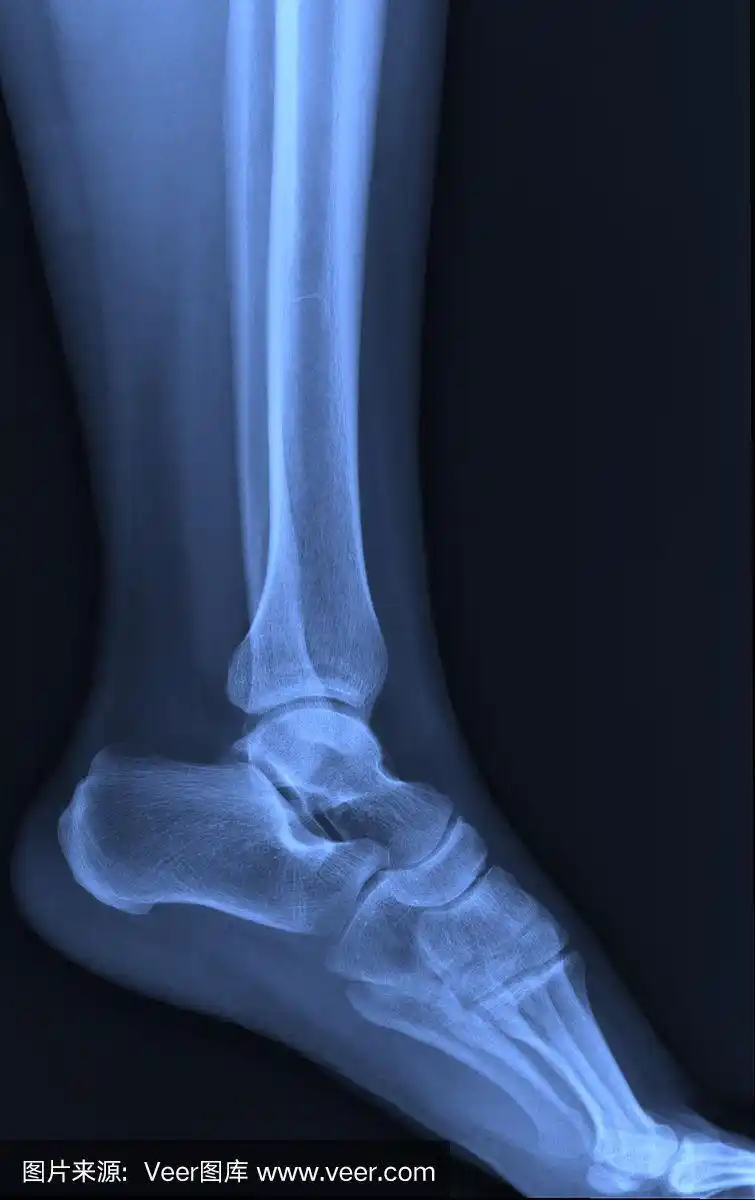

踝关节x线片或右踝关节ap和侧位片诊断踝关节骨折.